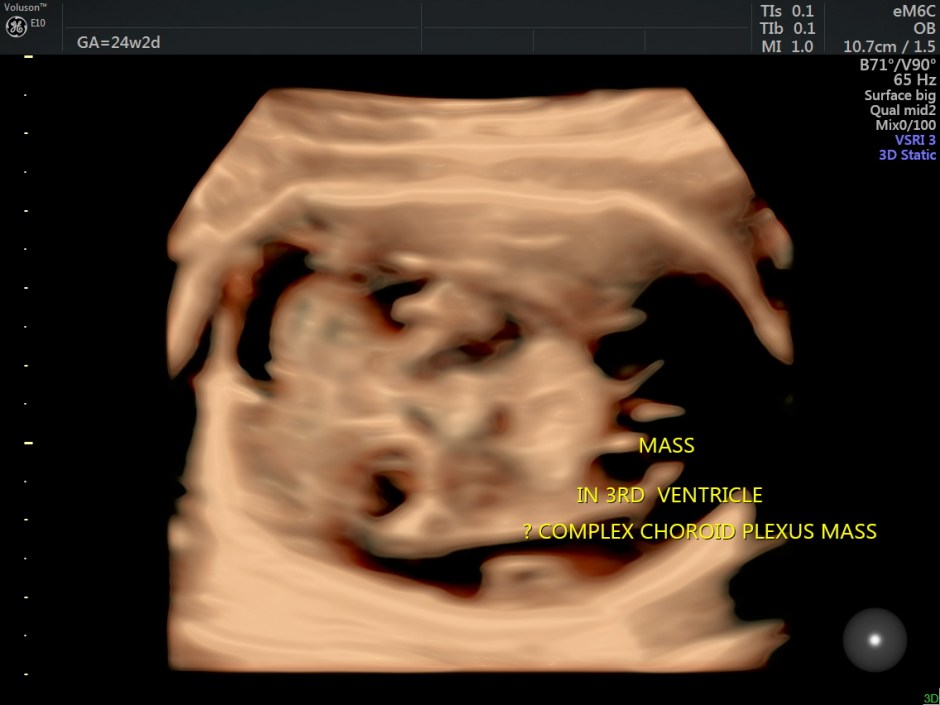

A careful look at the 3rd ventricle shows a solid mass.

Some reconstructed images are given below.

Choroid plexus papilloma (CPP) is a rare and benign tumor composed of epithelial cells that line the ventricular choroid plexus and correspond to 0.4%-0.6% of fetal intracranial tumors. CPP may develop in the lateral ventricle, third ventricle, and fourth ventricle. It is generally diagnosed during the third trimester and is always associated with unilateral or bilateral ventriculomegaly. CPP has slow growth and noninvasive behavior; however, because of its specific location, CPP can block the drainage of cerebrospinal fluid and cause hydrocephalus.

An echogenic mass involving the choroid plexus is visualized on US and MRI. Color Doppler imaging may be useful to show vascularization in the lesion.

In this patient, reconstructed images show the corpus callosum to be formed.